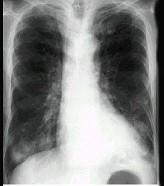

问题 女,52岁,曾患有鼻窦炎,最近发现咳嗽发热,影像学检查如图,最可能的诊断为 ( )

选项 A.多发性肺脓肿 B.浸润型肺结核并空洞形成 C.韦格肉芽肿 D.结节病 E.肺转移瘤

答案 C